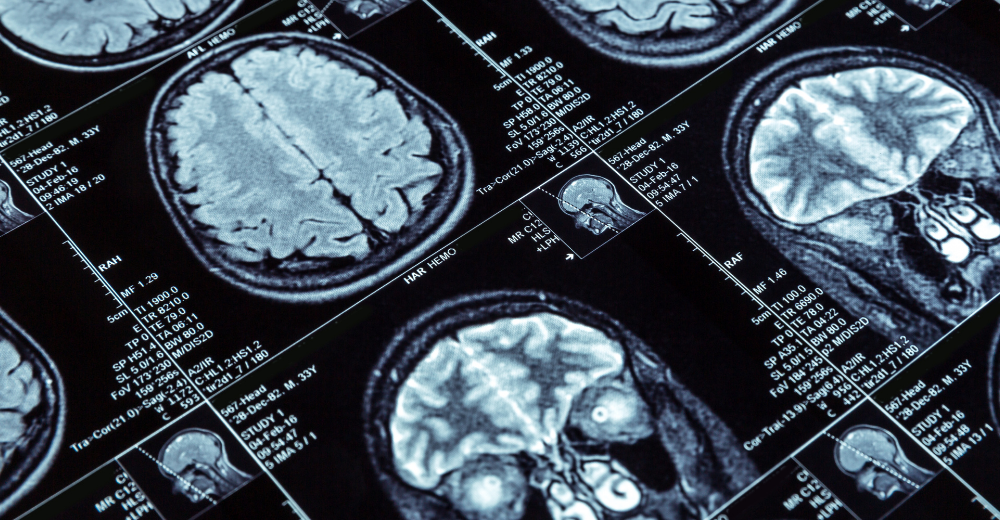

Durante una Risonanza Magnetica Encefalo e Tronco Encefalico presso il Poliambulatorio S-Medical Group di Sora, il paziente è collocato all’interno di un’apparecchiatura che assume la forma di un tunnel, nota come macchina a risonanza magnetica. Questa macchina emette campi magnetici che interagiscono con i protoni nel corpo. Successivamente, tramite onde radio, si generano segnali che vengono captati dalla macchina e trasformati in immagini dettagliate del cervello e del tronco encefalico.

Durante la Risonanza Magnetica Encefalo e Tronco Encefalico, l’energia si trasferisce attraverso l’interazione tra i campi magnetici e i protoni nel corpo. Le onde radio disturbano l’allineamento dei protoni, che rilasciano energia tornando alla loro posizione originale. Questa energia viene poi captata dalla macchina a risonanza magnetica e utilizzata per generare immagini dettagliate del cervello e del tronco encefalico.